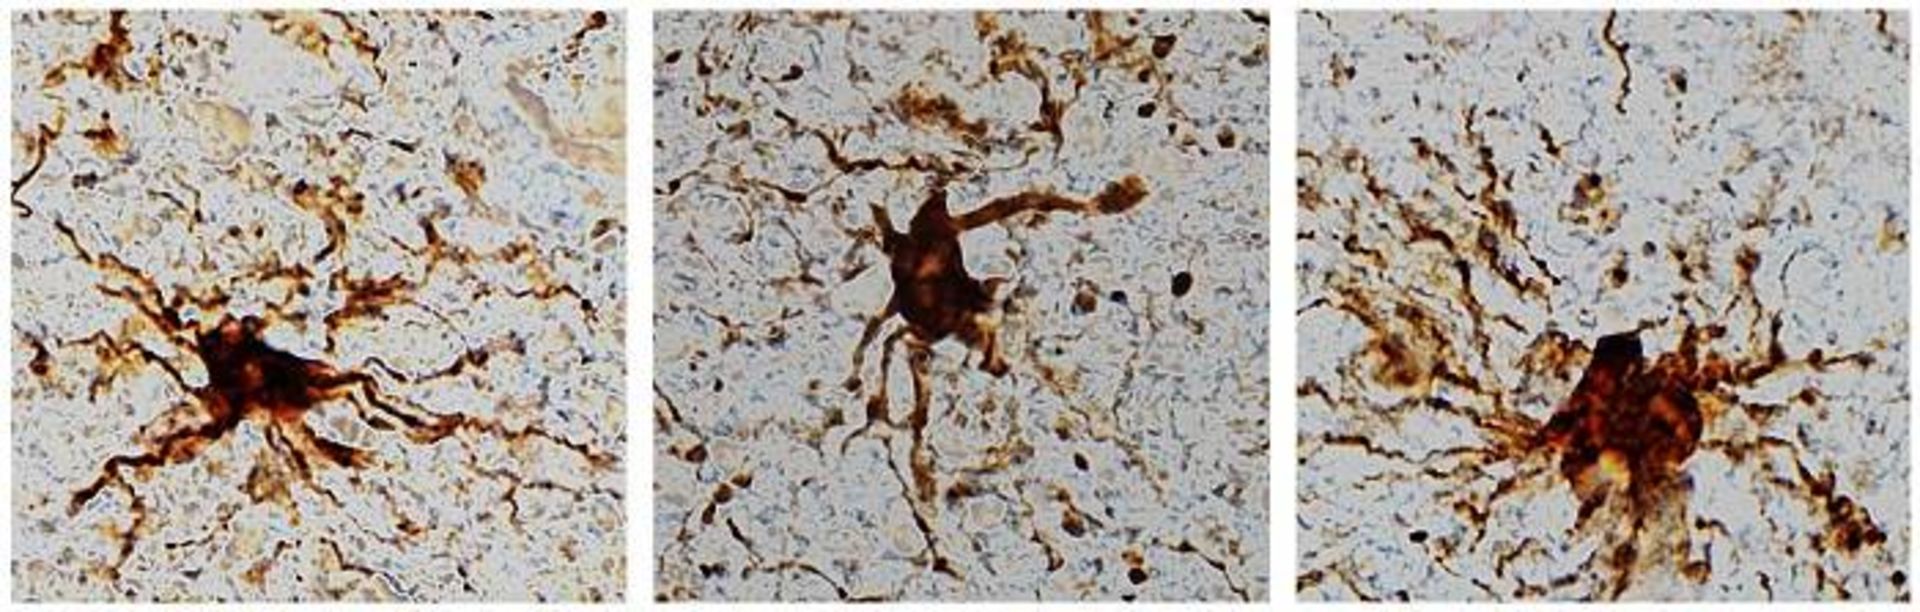

سلول‌ های گلیال پس از مرگ

سلول‌های گلیال پس از مرگ مغز انسان فعالیت خود را افزایش می‌دهند

لوئب و گروهش با مقایسه بیان ژن در بافت تازه مغز (که به‌عنوان بخشی از جراحی صرع از ۲۰ بیمار برداشته شده بود) با نمونه‌های مغز افراد متوفی، تفاوت‌هایی را پیدا کردند که ربطی به سن یا بیماری نداشت. آن‌ها از داده‌های بیان ژن که بعداً با بررسی‌های بافت‌شناسی بافت مغز تأیید شد، برای درک تغییرات خاص سلول در طول زمان از زمان مرگ استفاده کردند. درحالی‌که بیشتر فعالیت‌های ژنی طی ۲۴ ساعت ثابت ماند، سلول‌های عصبی و فعالیت ژنی آن‌ها به‌سرعت متوقف شد؛ اما بیان ژن سلول‌های گلیال افزایش پیدا کرد و فرایند ایجاد زائده در آن‌ها قابل مشاهده بود.

این مسئله در آغاز عجیب به نظر می‌رسد؛ اما با توجه به اینکه سلول‌های گلیال مانند آستروسیت‌ها و میکروگلیاهایی که ضایعات را می‌خورند، زمانی‌که مشکلی پیش می‌آید، برای اقدام فراخوانده می‌شوند، کاملا منطقی است. مرگ شبیه وضعیتی است که گویی مشکلی پیش آمده است. لوئب می‌گوید:

اینکه سلول‌های گلیال پس از مرگ بزرگ می‌شوند، با توجه به التهابی بودن آن‌ها و اینکه وظیفه‌ی آن‌ها پاک‌سازی مواد زائد پس از آسیب‌های مغزی مانند کمبود اکسیژن یا سکته است، خیلی عجیب نیست.